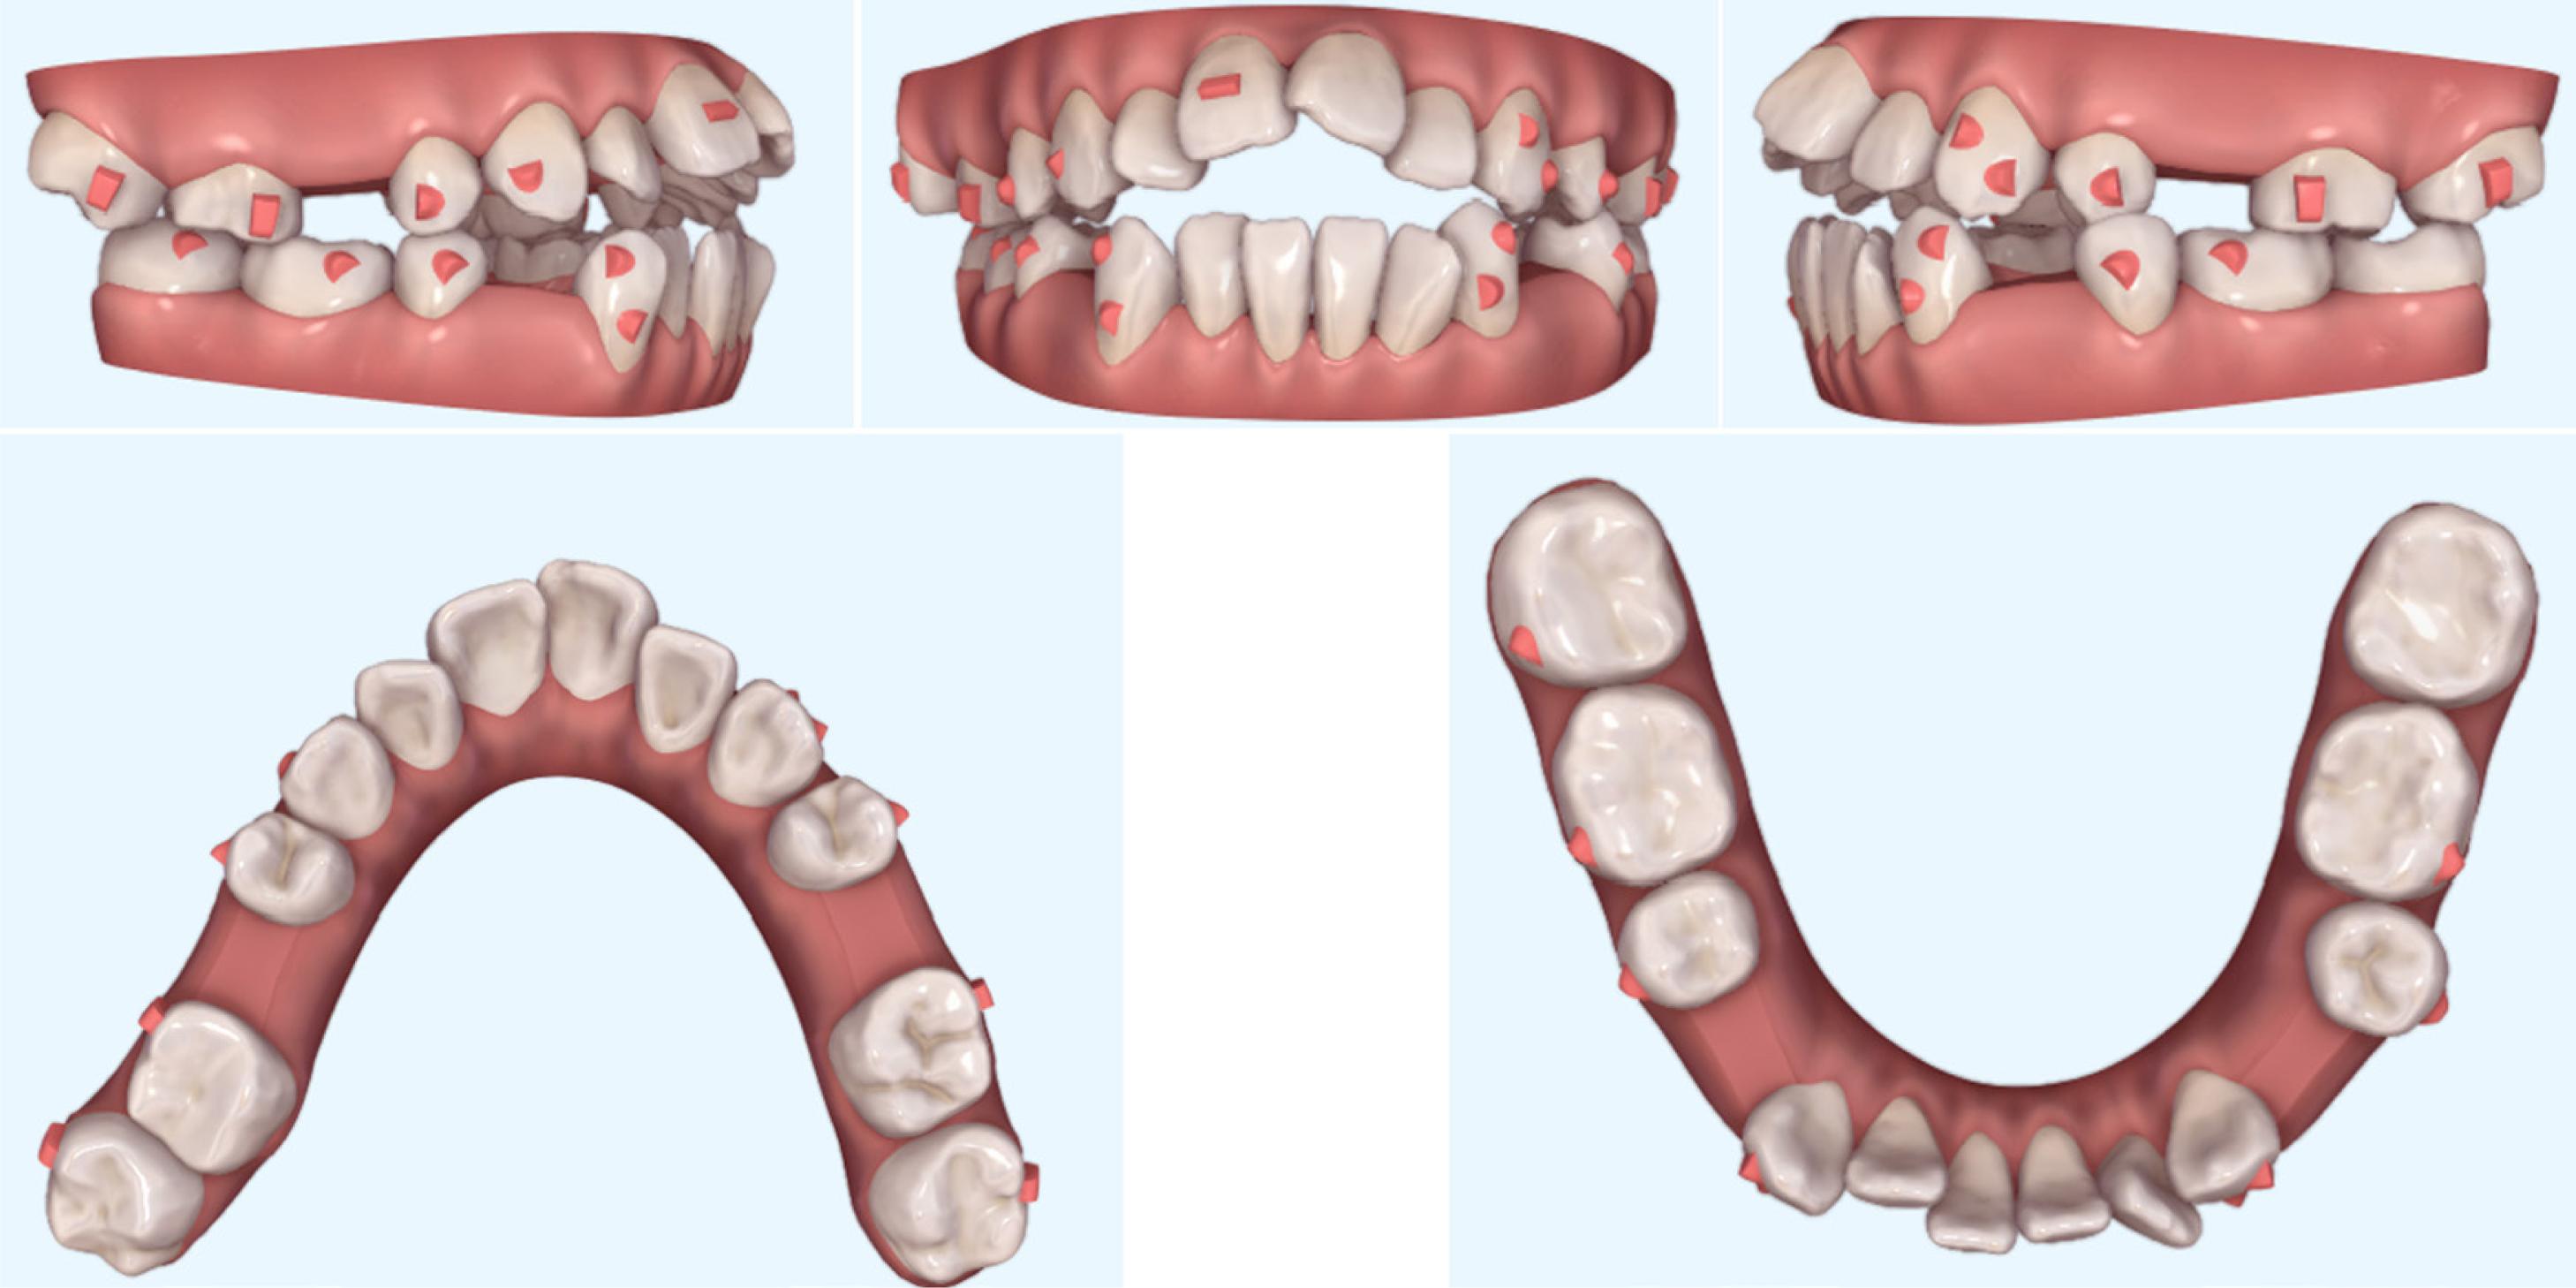

The treatment commened by extracting the four premolars. The goals of the initial phase were to align and level the dental arches, close the extraction spaces, and close the open bite. In the upper arch, 14, 24, 13, and 23 were retracted, leaving a space at the mesial area of 13 and 23. The anterior teeth were aligned, and 8° of lingual root torque was added prior to en-masse retraction. The teeth 16 and 26 were moved first, allowing further mesialisation of 17 and 27, until 16 and 26 contacted 14 and 24, respectively. Optimised retraction attachments were applied to the upper canines, as well as optimised anchorage attachments and vertical rectangular attachments on the upper posterior teeth. An extrusion attachment was designed and placed on the upper right incisor through an automated process. In the lower arch, the treatment plan was to retract 33 and 43, thereby leaving space mesial to 33 and 43 (which improved aligner grip), adding 10° of lingual root torque before en-masse retraction of the incisors. The G628 solution for optimised retraction attachments was used on the canines and optimised anchorage attachments on the lower posterior teeth. The patient wore bilateral Class III, 3.5-ounce elastics, full time throughout the treatment phase. It was planned to intrude the upper posterior teeth by approximately 2 mm, extrude the upper anterior teeth by approximately 1.5 mm, and finally achieve an overbite of roughly 3 mm. In addition, it was planned to expand the maxillary arch in order to co-ordinate the arch forms. Palatal crown torque of 17 was necessary to achieve a normal buccal overjet of the right posterior teeth. The pre-treatment ClinCheck treatment plan is presented in Figure 5.

Pre-treatment ClinCheck treatment plan (Align Technology, Santa Clara, CA, USA).